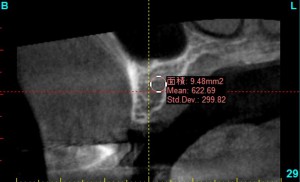

その際、クリニックでは、院内で撮影したCTをインプラント治療シュミレーションソフトで分析し、下記のような評価法と対比させ、骨の状態を判断に用いています。

骨の評価を5段階に分類し、その情報をもとに、手術方法を微妙に変化させます。

たとえば、このインプラントをいれる部分の骨は、mean 932となっているため、D2の十分な骨の硬さがあるため、安定したインプラントになりやすく、また、インプラントが安定するのに、短期間で済むことがわかり、インプラントの治療の期間が短くて済むと予測できます。

mean値を確認しながら、骨の状態を調べ、把握します。